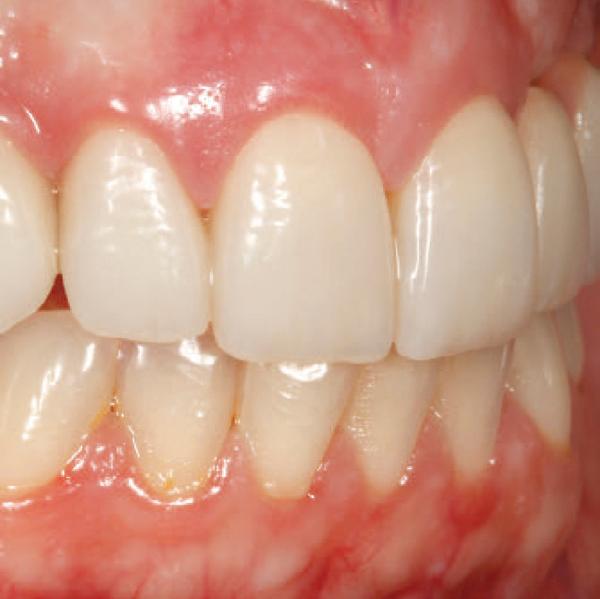

A significant number of people are unhappy with their smile, which has a considerable psychosocial impact. Although many seek cosmetic dental treatment, costs, fear and duration of total treatment are often barriers to the patients. Nevertheless, many could benefit from small and subtle changes to their teeth. With simple direct and freehand techniques, quick but significant results can be obtained that ultimately greatly improve the overall smile aesthetics.

The restoration of abfractions in the anterior area is important for aesthetic appearance especially in patients with high smile lines. Moreover, restoring abfractions strengthens the cervical area of the tooth, prevents further loss of enamel and ameliorates unpleasant sensitivity.

Black triangles and diastemas can cause entrapment of the food and accumulation of bacteria, which leads to gingivitis and ultimately periodontitis. By eliminating the black triangles and diastemas with composite bonding, the dentist not only improves the aesthetics, but also protects the long-term health of the periodontal tissues.

Worn canine cusp restoration is of special functional importance. Creating functional canine guidance with a minimally invasive composite addition to the canine cusp will protect the posterior teeth during lateral movements of the jaw. Incisal wear restorations return the youthful appearance to the smile and prevent further loss of enamel and exposure of the dentinee.

Restoring incisal wear and closing diastema with G-aenial A’CHORD. Courtesy of: Dr Aleksandra Slacan, Poland

Reshaping of teeth and diastema closure with G-aenial A’CHORD. Courtesy of: Dr Andres Silva, Spain